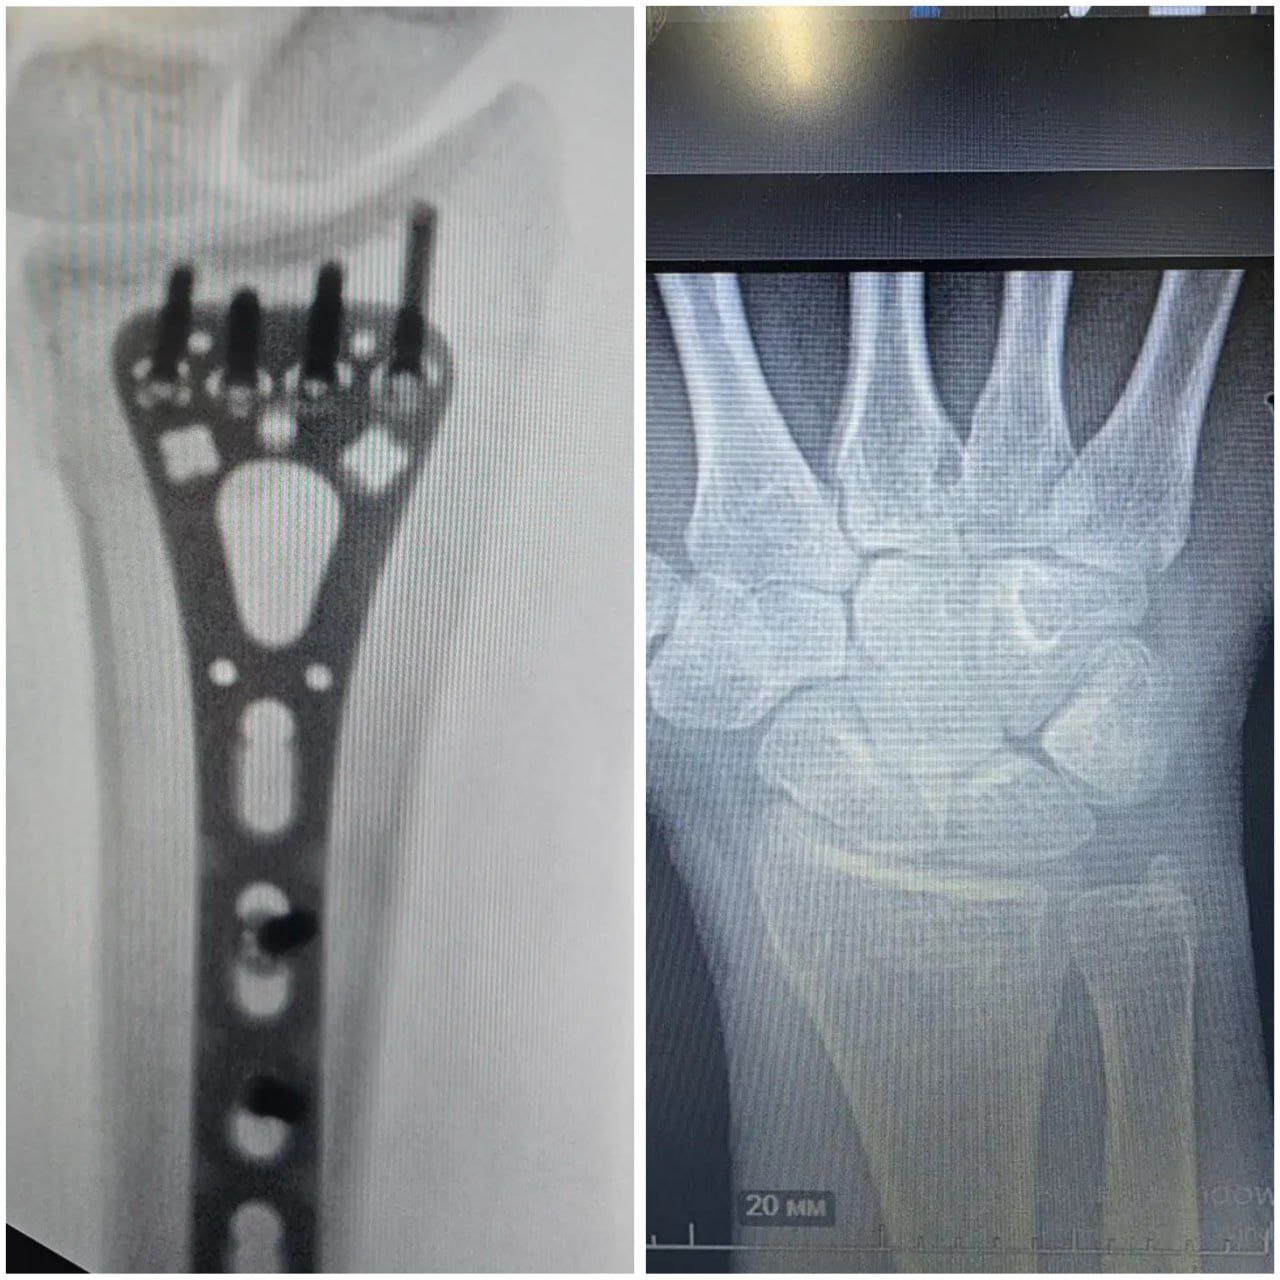

За весь период врачи провели уже более 1400 операций. Одна из пациенток попала на стол к хирургам после ДТП на мотоцикле. Она получила перелом лучевой кости со смещением. Для восстановления анатомии кости провели остеосинтез: зафиксировали ее фрагменты титановой пластиной и винтами, рассказал заведующий Центром реконструктивной микрохирургии кисти Иван Быркэ

Через 6 месяцев рука полностью восстановилась — девушка вернулась к привычному образу жизни.